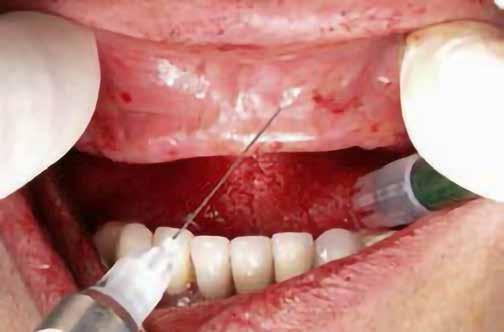

Hathetes gyógyulás után a lágyszövetek kiválóan gyógyultak, és minden implantátum megfelelően osszeointegrálódott, amelyet a radiológiai vizsgálat is megerősítetett (9. és 10. ábra).

Nyitott kanalas lenyomatvételi fejeket csatlakoztattunk az implantátumokhoz, és elasztomer lenyomat-anyagot fecskendeztünk köréjük és a lenyomatkanálba, hogy egyfázisú lenyomatot vegyünk. A minta laboratóriumi elkészítését követően a kimart vázra kerámia leplezés került, amelyet megfelelő festéssel tettek még természetesebbé. Ezt követően a pótlást közvetlenül az implantátumokhoz csatlakoztattuk, majd ellenőriztük a kontaktpontot és az okklúziót. Minden csavart 35 Ncm-es nyomatékra húztunk, majd a csavarnyílásokat teflonszalaggal és fényre kötő kompozittal zártuk (11. ábra).